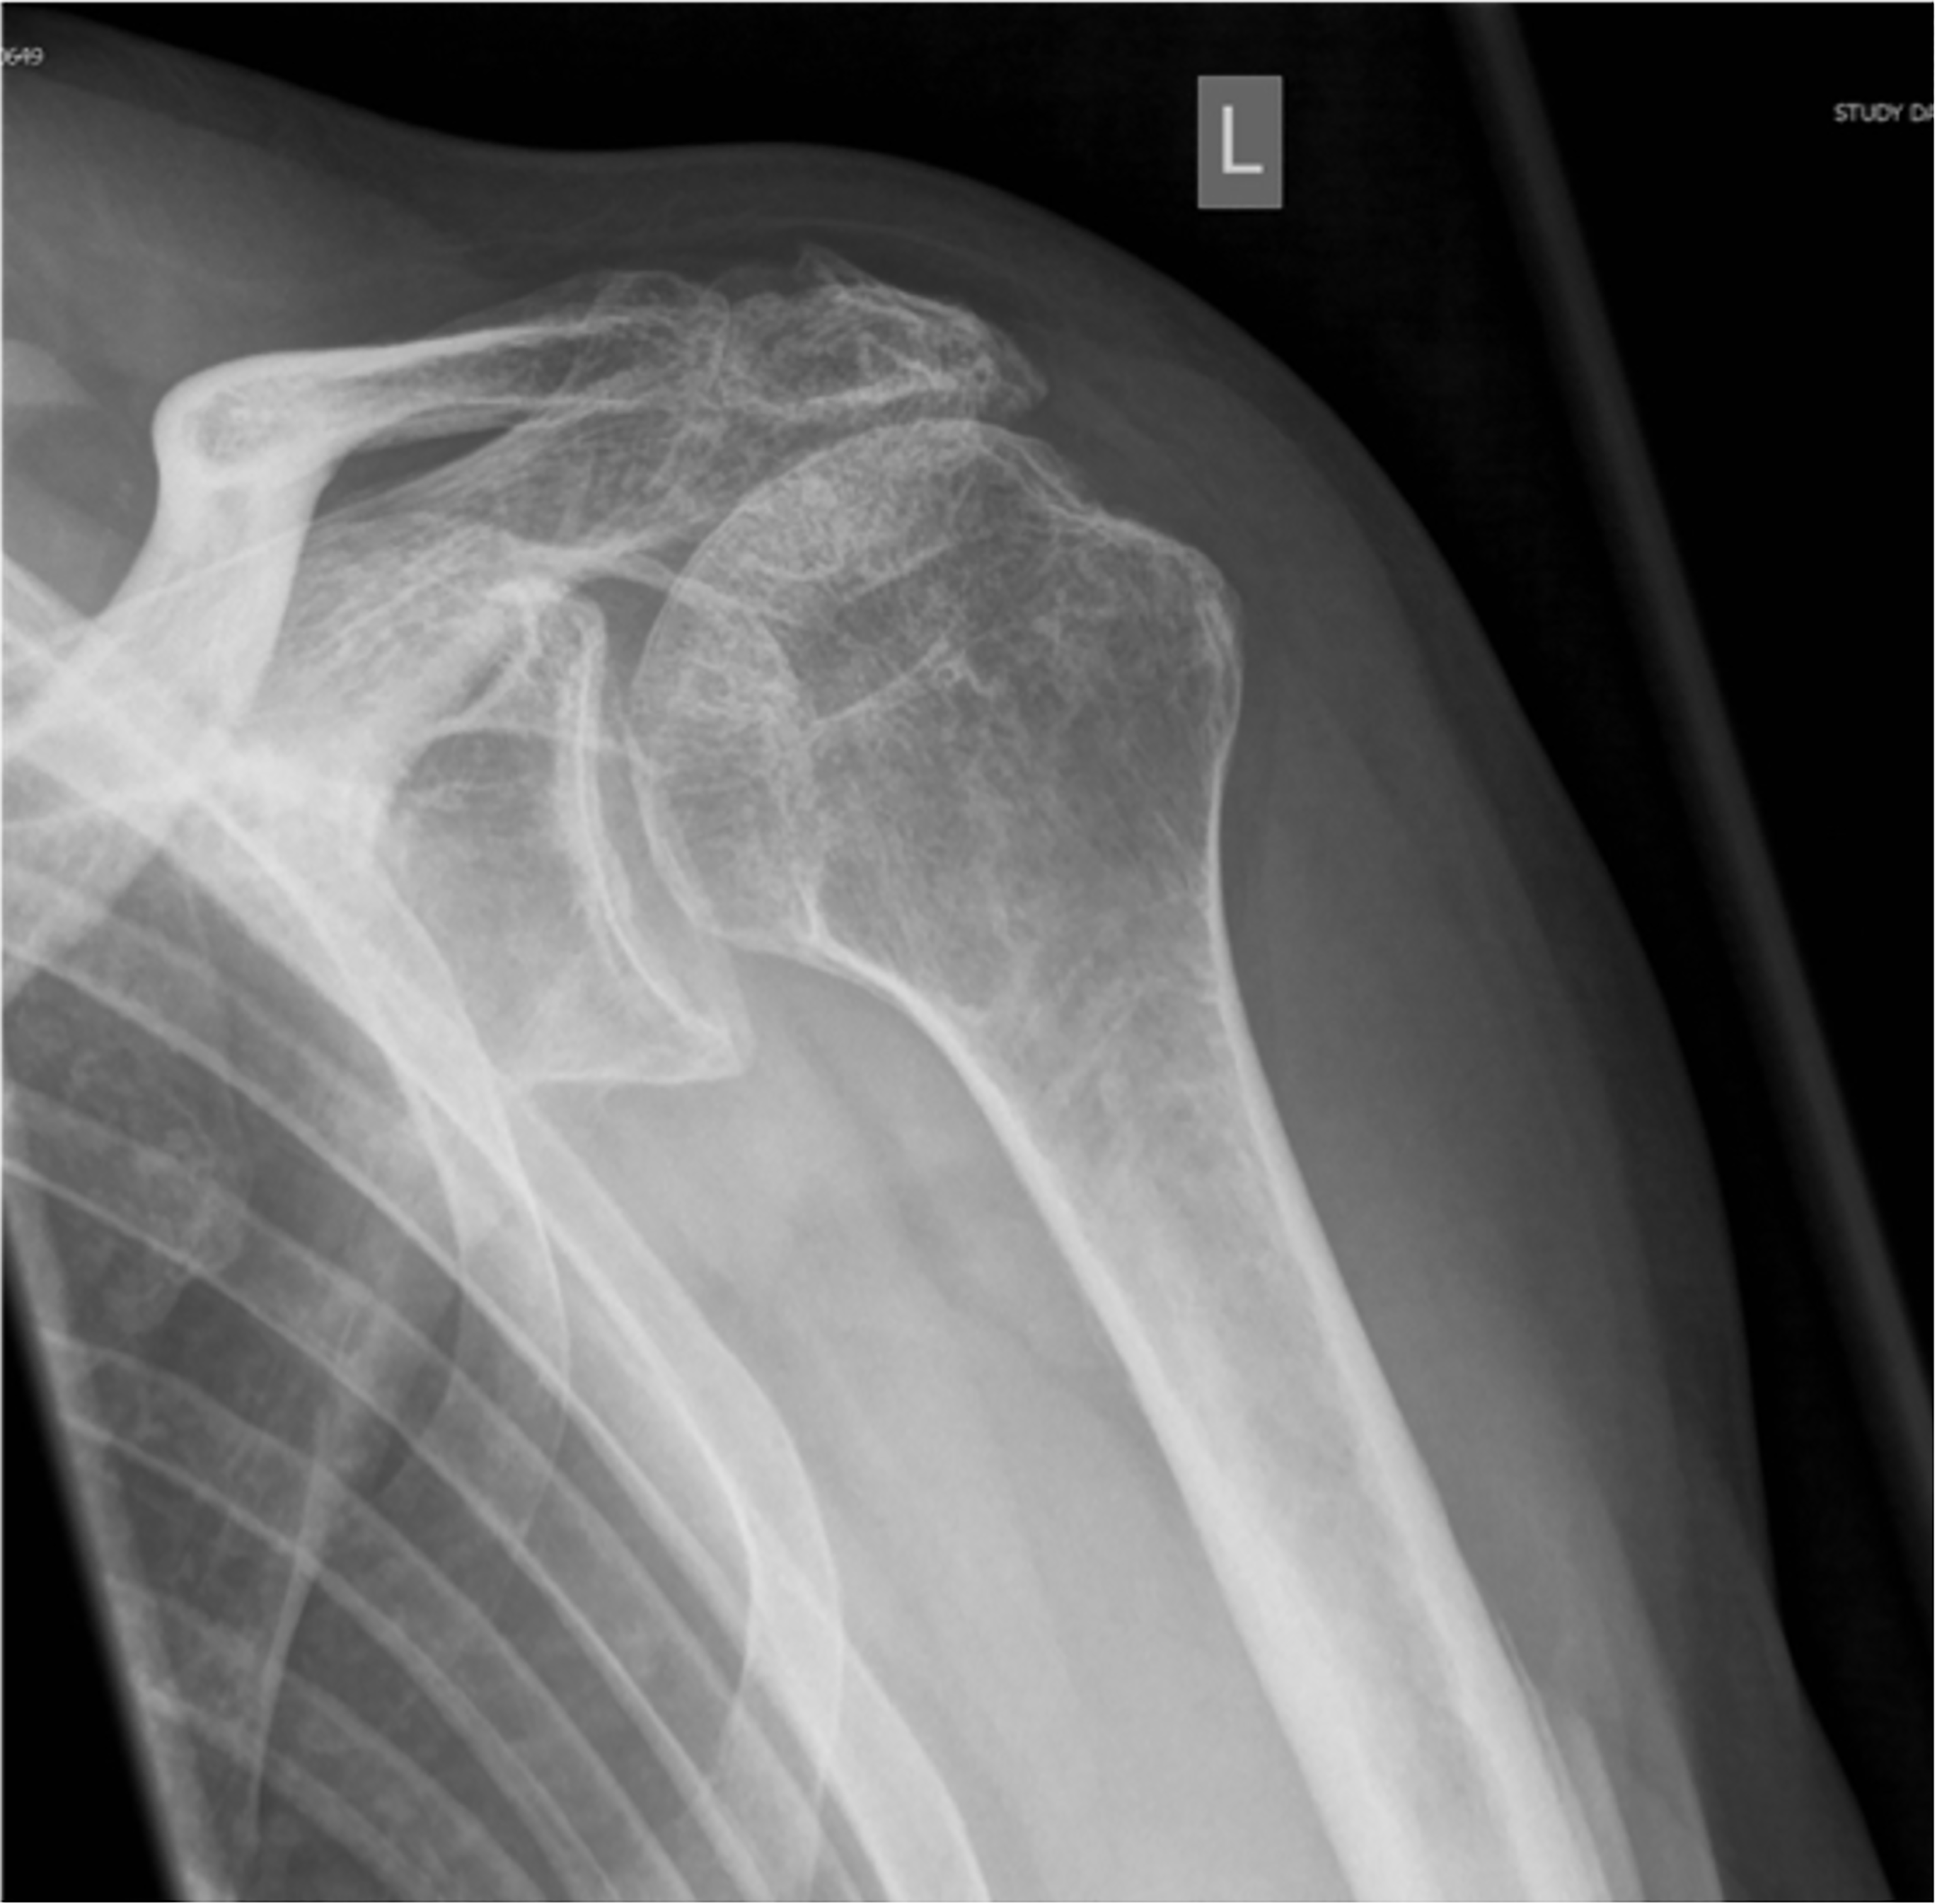

Beauty of scientific process is that every experiment should be verified and replicated. Since the first publication in 2012, several clinical studies about this treatment modality can be identified (9,11,16,17,18,19,20,21,22,23,24,25,26,27,28,29). Some authors published results with a longer follow-up on the same patients group (15,28). Additionally, several comprehensive literature search, systematic reviews and meta-analysis on subacromial spacer implantation were published in the last years (30,31,32,33). One additional systematic review article assessed and compared the outcome of different treatment modalities for irreparable posterosuperior rotator cuff tears including subacromial spacer implantation (34). Available studies reported the results of more than two-hundred cases in patients 50-85 years old with posterosuperior irreparable rotator cuff tear treated with subacromial spacer implantation. Results showed improvement of the mean Constant score from 35 preoperatively to 65 postoperatively. Reported pain improvement is from 3,5 to 5 points out of 10 in VAS scale. Ability to perform activities of daily living increased from 6 to 13,7 points out of 20 as assessed from Constant score. However, as one can expect, improvement of abduction strength is very limited. These results are reported at 6 months and further sustained at all subsequent time periods up to 5-years follow-up period (Figure 2). Reported results are actually comparable to the other treatment options (35). Interestingly, patients included in the subacromial spacer studies usually have more significant shoulder function impairment compared to patients treated by other techniques as has been shown by lower Constant score preoperatively.

In the future, several properties of the implant effect and outcome of the procedure have to be addressed. It is not clear, why the positive effect of the biodegradable spacer continues beyond the time of its degradation period, which begins at 3 months and dissolves by 12 months (16,29). In this regards, influence of the spacer implantation on the acromiohumeral distance (AHD) is interesting. It was noted that AHD increased immediately after spacer implantation (Figure 3) (11).